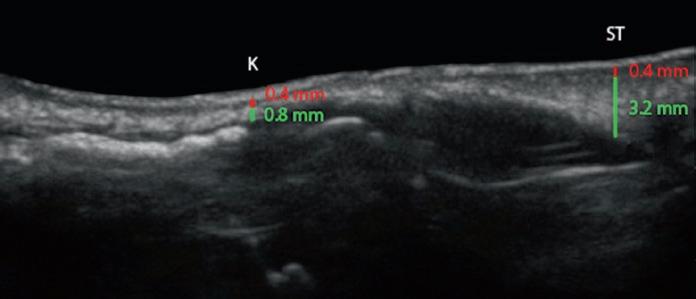

Sonogram analysis of the nasal skin is an extremely valuable tool, both for preop and postop analysis in rhinoplasty surgery. Patients found to have thin skin had a dermal thickness at the keystone junction (K) of 0.2 mm (0.1–0.4 mm), compared with 0.36 mm (0.28–0.40 mm) for normal skin and 0.48 mm (0.42–0.63 mm) for thick skin (Fig. 1.20) (Kosins and Obaghi 2017). This difference in thickness also existed in the supratip and tip areas, but these areas were also affected by the oiliness of the skin. Overall, patients with skin that was determined to be oily had a dermal thickness that was 25% thicker at the supratip and 34% thicker at the tip area. Soft tissue thickness underlying the dermis was variable. Patients of non-Caucasian background were more likely to have a thicker soft tissue layer. Patients with thick skin can be divided into those with thick dermis, thick underlying soft tissue, or both.

Fig. 1.20 Sonograms of nasal skin, showing the thickness of the dermis (red ) and SMAS ( green). (a, b) Thin skin. (c , d) Medium skin. (e, f ) Thick skin. K keystone junction; ST supratip; T tip (Sonograms courtesy of Aaron Kosins, MD.)